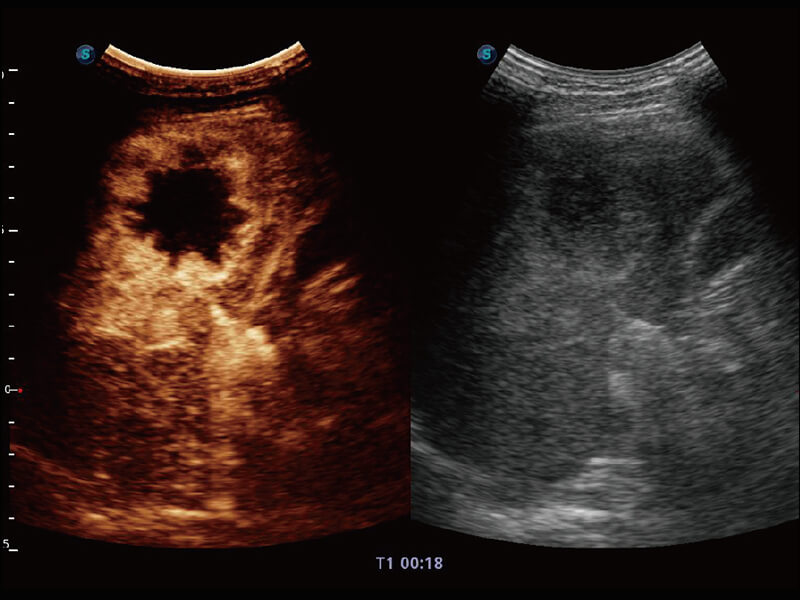

成像功能

S60探头工艺,从前端信号处理每一个环节采集无损声学数据,真实还原组织原貌,再现解剖细节。